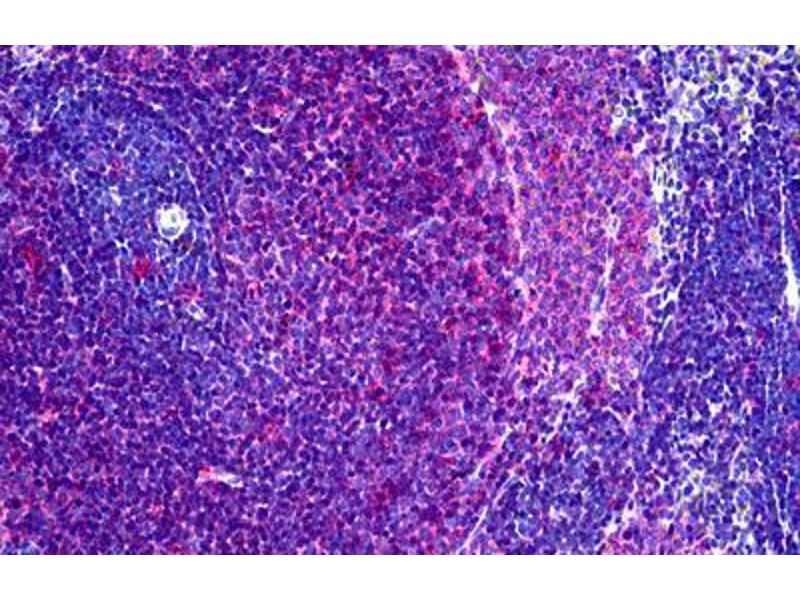

Flow Cytometry (FACS), Immunohistochemistry (Frozen Sections) (IHC (fro)), Immunohistochemistry (Paraffin-embedded Sections) (IHC (p)), Western Blotting (WB), Immunohistochemistry (IHC)

Recognizes a monomorphic determinant of the rat I-A antigen present on B lymphocytes, dendritic cells, some macrophages and certain epithelial cells. Reacts with certain mouse strains of MHC haplotypes k and s. Analysis of recombinant mouse strains showed that the determinants mapped to the I-A region. Does not react with the BDIX rat strain. Expression is polymorphic in mice. This product is routinely tested in flow cytometry on rat splenocytes.

Approved: Flo (1:50 - 1:100), IHC, IHC-Fr, IHC-P (10 μg/mL), WB

Usage: Flow Cytometry: Use 10 μL of the suggested working dilution to label 10^6 cells in 100 μL. Method sheets are available on request. Immunohistology: This product does not require antigen retrieval using heat treatment or protein digestion prior to staining of formalin-fixed paraffin-embedded sections, but results may be enhanced with heat treatment using 0.01M citrate buffer  pH 6.This clone has also been described reacting with paraffin-embedded material following PLP fixation (periodate-lysine-paraformaldehyde)